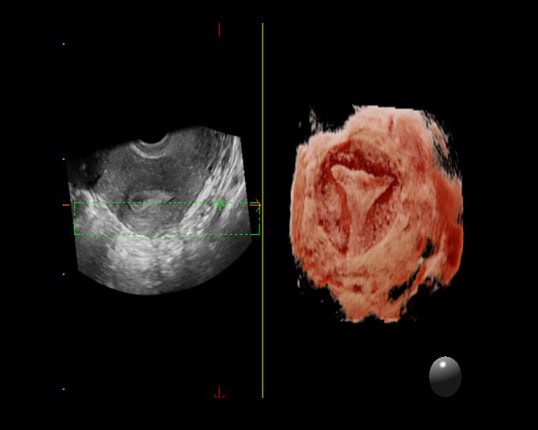

XLight - phần mềm siêu âm sản 3D/4D chuyên sâu cho mặt thai nhi mịn, chân thật. Nhờ công nghệ bố trí nguồn sáng ảo và khả năng tái tạo bề mặt.

may sieu am mylab x7

Đầu dò Phụ khoa 4D - tái tạo 4 chiều bên trong phụ khoa.